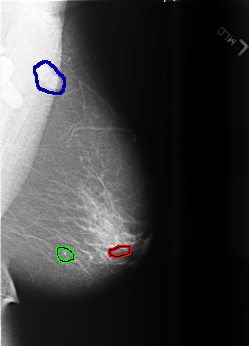

FILE: B_3466_1.LEFT_MLO.OVERLAY

TOTAL_ABNORMALITIES 3

ABNORMALITY 1

LESION_TYPE CALCIFICATION TYPE FINE_LINEAR_BRANCHING DISTRIBUTION CLUSTERED-LINEAR

ASSESSMENT 4

SUBTLETY 2

PATHOLOGY BENIGN

TOTAL_OUTLINES 1

BOUNDARY

ABNORMALITY 2

LESION_TYPE CALCIFICATION TYPE PLEOMORPHIC DISTRIBUTION CLUSTERED

SUBTLETY 4

ABNORMALITY 3

LESION_TYPE MASS SHAPE LYMPH_NODE MARGINS CIRCUMSCRIBED

ASSESSMENT 0

SUBTLETY 5

PATHOLOGY UNPROVEN